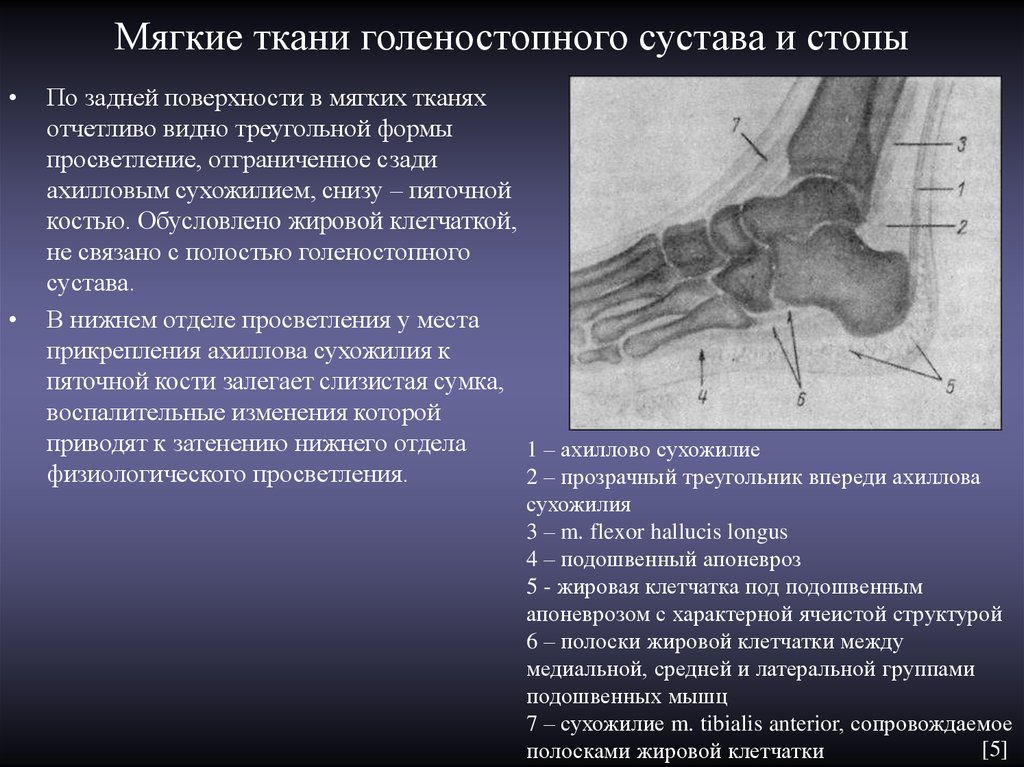

Анатомические фото голеностопного сустава и его суставных поверхностей